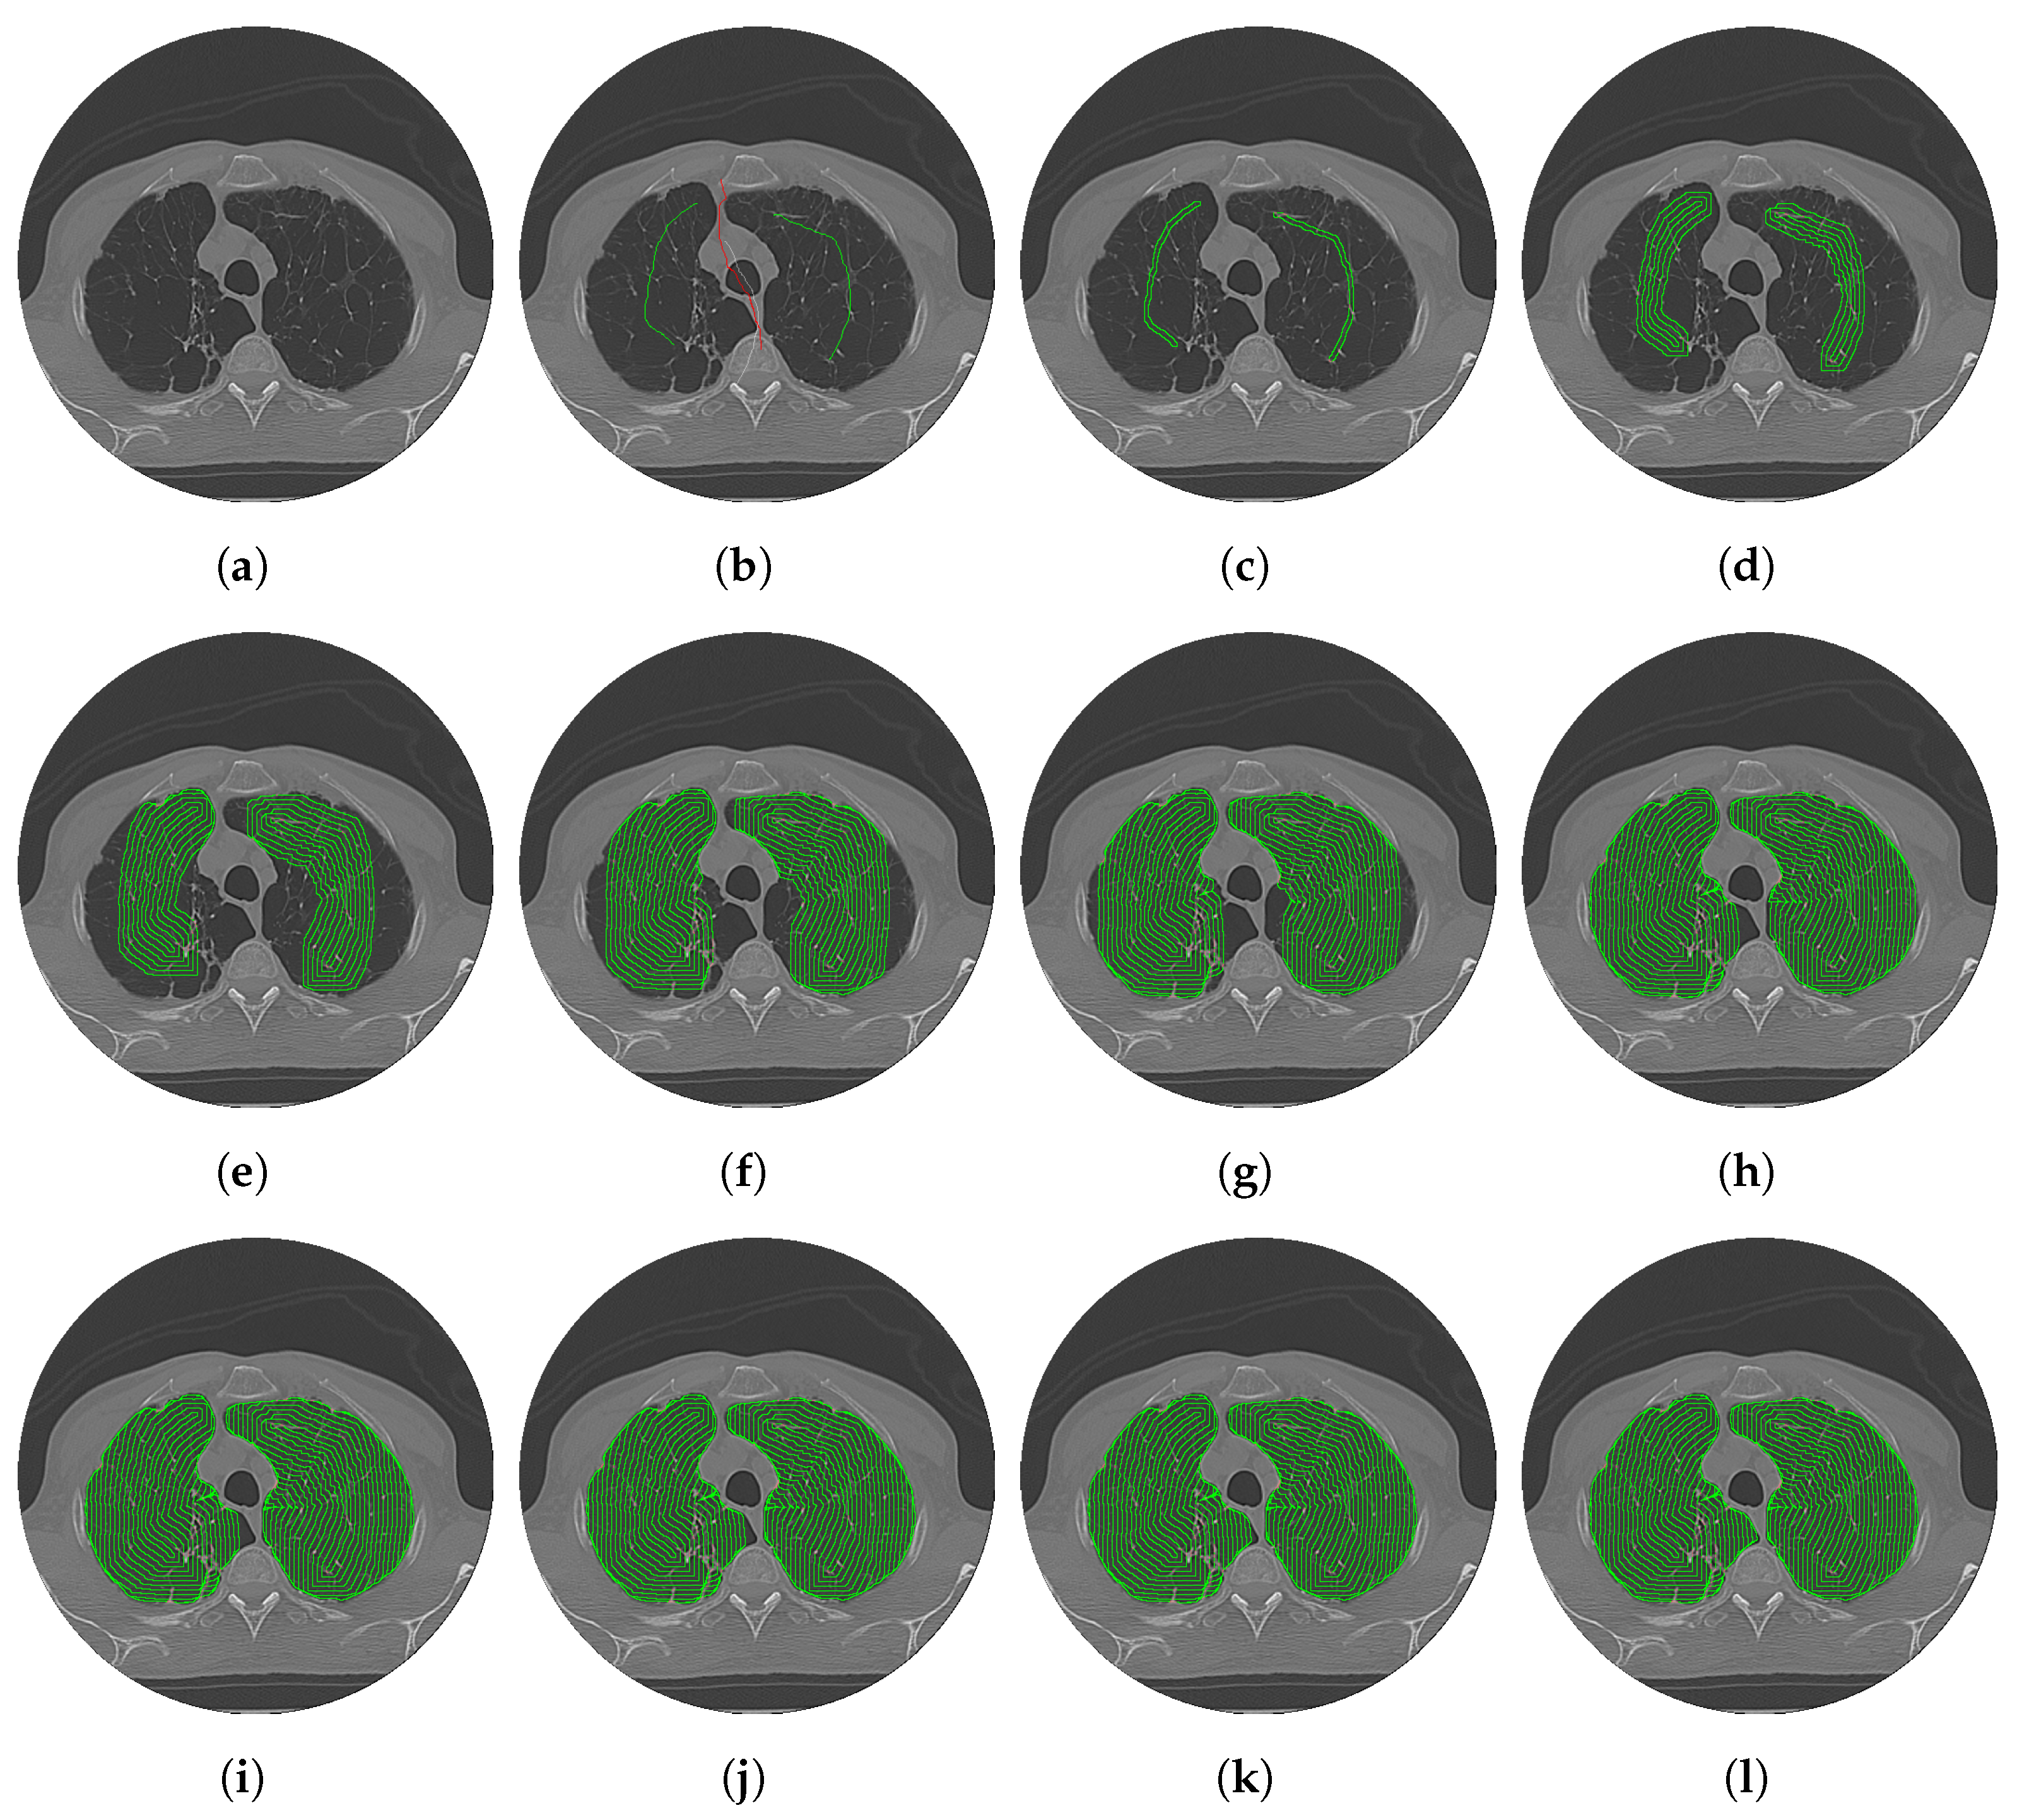

3.1. CDAC Settings

3.2. Individual Analysis Approach

3.2.1. Analysis Between CDAC Versions—Individual Approach